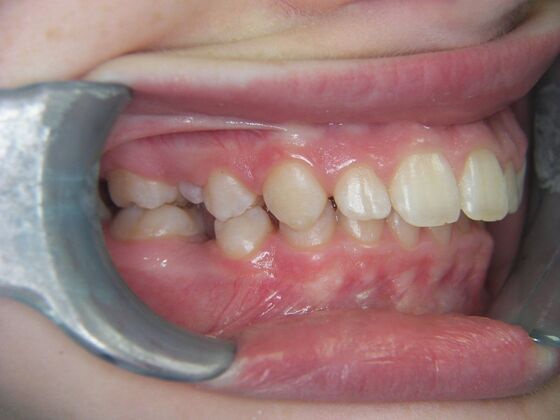

Patient is 9 years old and presents with 100% overbite and blocked out upper and lower lateral incisors. Both upper central incisors are palatally inclined causing a lack of space available for most anterior teeth. Advised her parents that she needs Phase I Interceptive Orthodontic treatment to provide room for all upper and lower front teeth. Phase I treatment was begun and finished, then began Phase II treatment shortly thereafter to finalize case. Removable retainer were fabricated for retention.